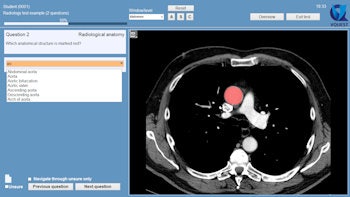

Example of an "indicate question" in VQuest. The student is asked to mark an anatomical structure in the volumetric image. Students can scroll through the image, change contrast settings manually or with the preset window/level menu, or change viewing direction by clicking the buttons (A, S, and C). The teacher decides which manipulation tools the students are allowed to use during the test or for a particular question. All images courtesy of Dr. Cécile Ravesloot.